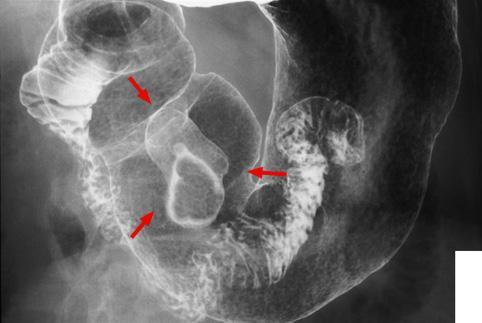

疾病(病理主体)的分类肿瘤样病变/其他

部位(按器官分)胃(部位)/前庭

检查方法X线

肿瘤最大直径30~34